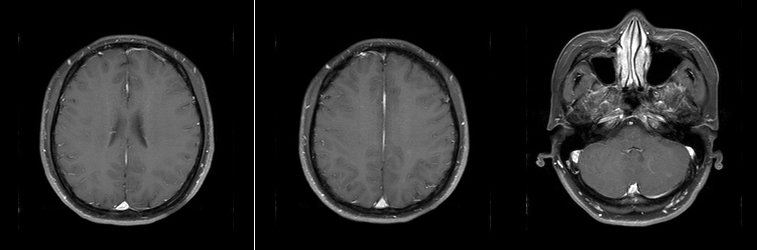

• 头颅MR(2024年4月14日):颅内多发结节状异常信号,大者位于左侧小脑板球,大小约1.1cm×1.0cm,M灶可能,请结合临床。

乳腺cr是什么双优标杆!从PD到18 个月达颅内CR,瑞波西利改写32岁HR+/HER2-晚期乳腺癌患者命运_https://www.jmylbn.com_新闻资讯_第6张

图 2024年4月14日头颅MR